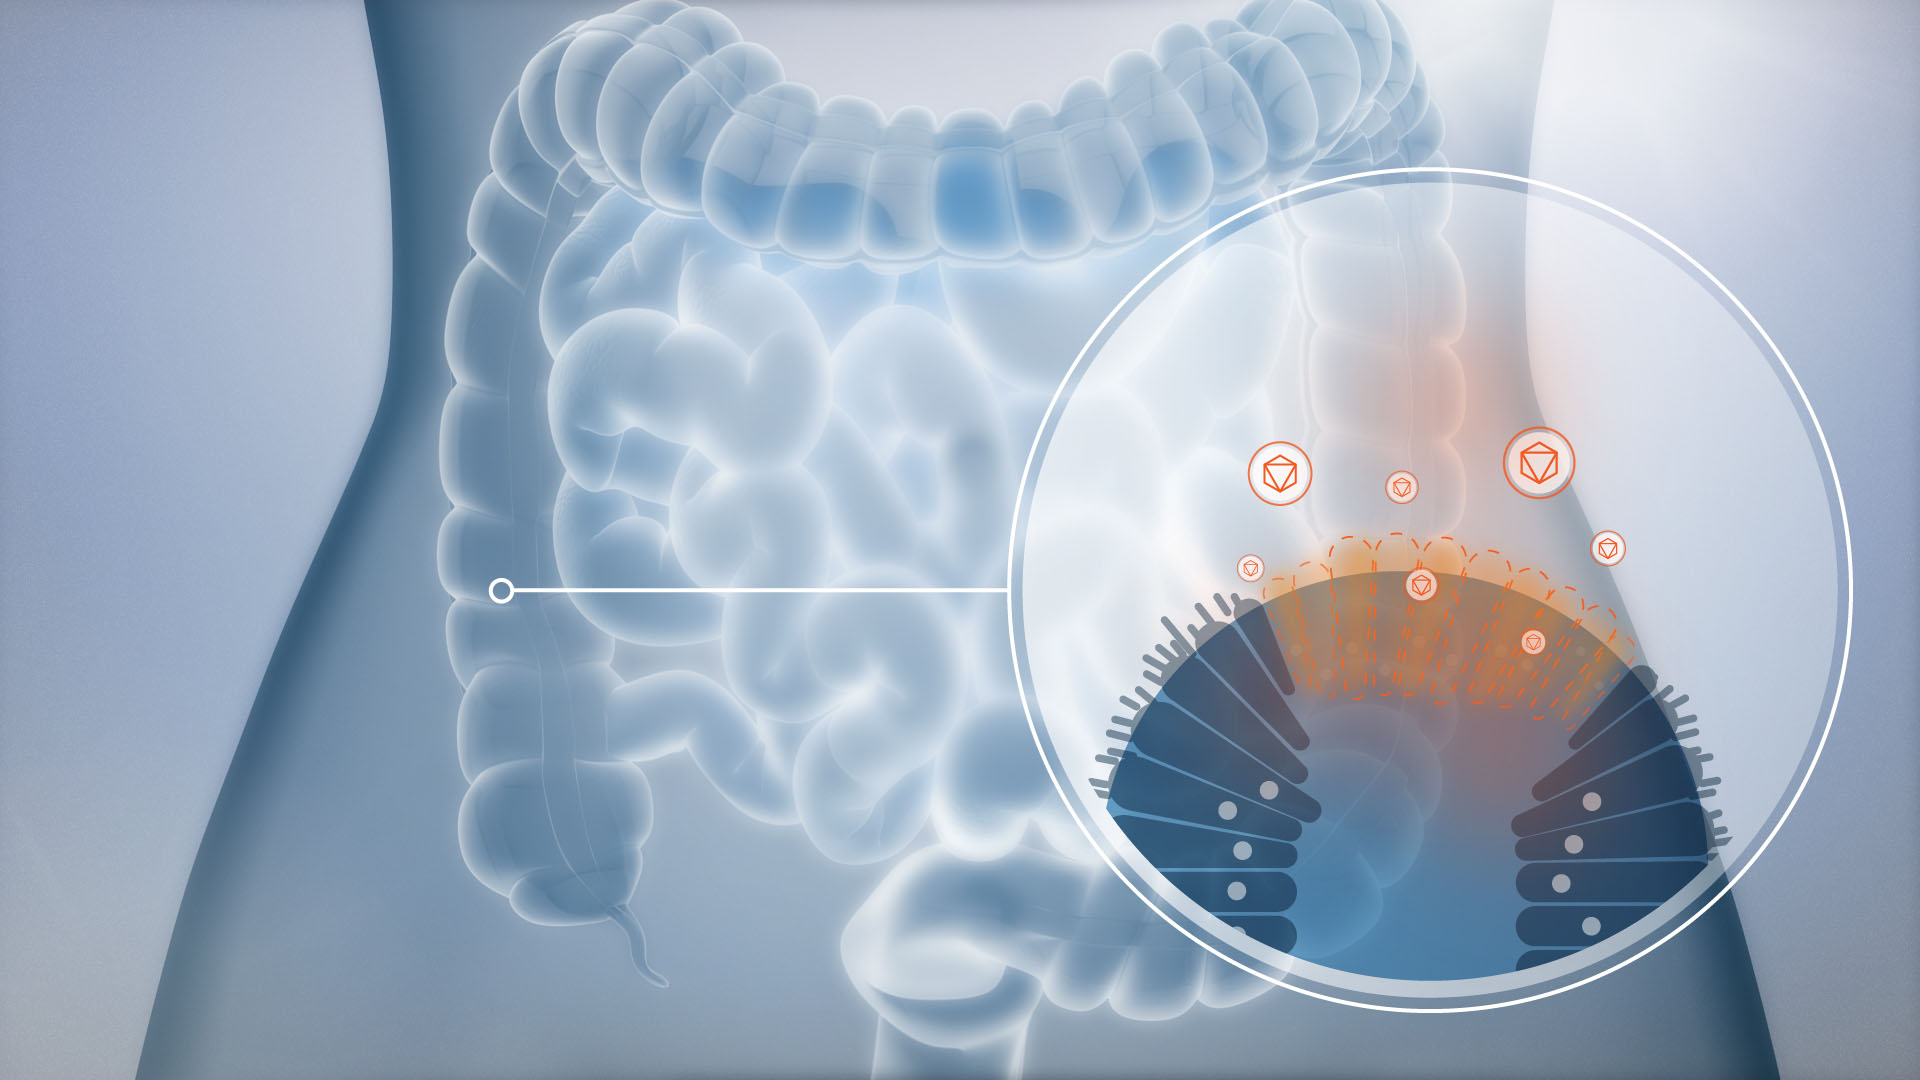

3D-WORKS

Manchmal muss es einfach 3D sein. Auch wenn sich in unseren 2D Animationen mehr 3D versteckt als man denkt, sind unsere realistischen Renderings immer etwas Besonderes. Speziell auf dem Gebiet der Medizin haben wir schon viele Projekte in 3D realisiert. Auch wenn wir davon hier nur wenig öffentlich zeigen dürfen.